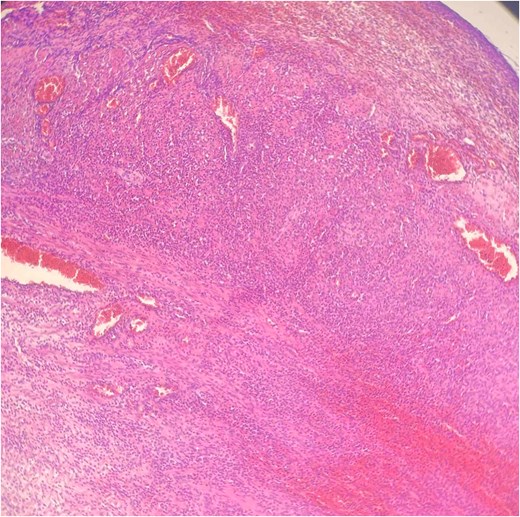

Histopathology confirmed gangrenous appendicitis with perforation (Figs 1 and 2). The postoperative course was uneventful; peristalsis returned on Day 2, with meticulous follow-up of laboratory parameters, gradual mobilization and restauration of bowel function from Days 3–7, and the patient was discharged on Day 7 in good condition.

Hematoxylin Eosin (HE) stain 100× transmural acute inflammation with peritonitis.